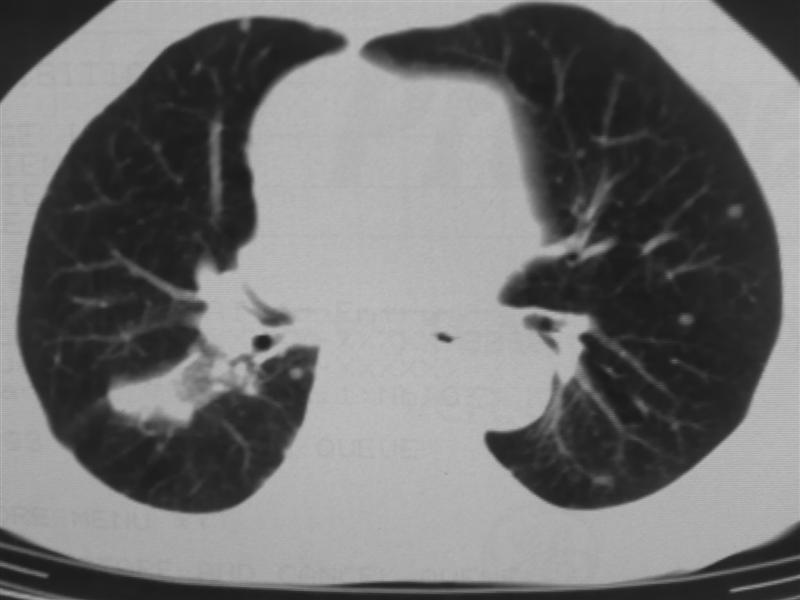

标题: CT10080:F76Y,各位老师发表高见!!! [打印本页]

标题: CT10080:F76Y,各位老师发表高见!!!

右下肺周围型肺癌伴双肺右侧叶间 胸膜及右肺门淋巴结转移

考虑:肺癌伴肺、胸膜 纵隔淋巴结转移可能性大!